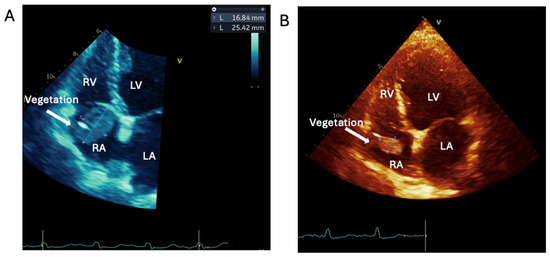

1.1.2. Case 2

2.2. Logistical Management Challenges in a Non-Compliant High-Risk Young PWID with Relapsing Right-Sided IE